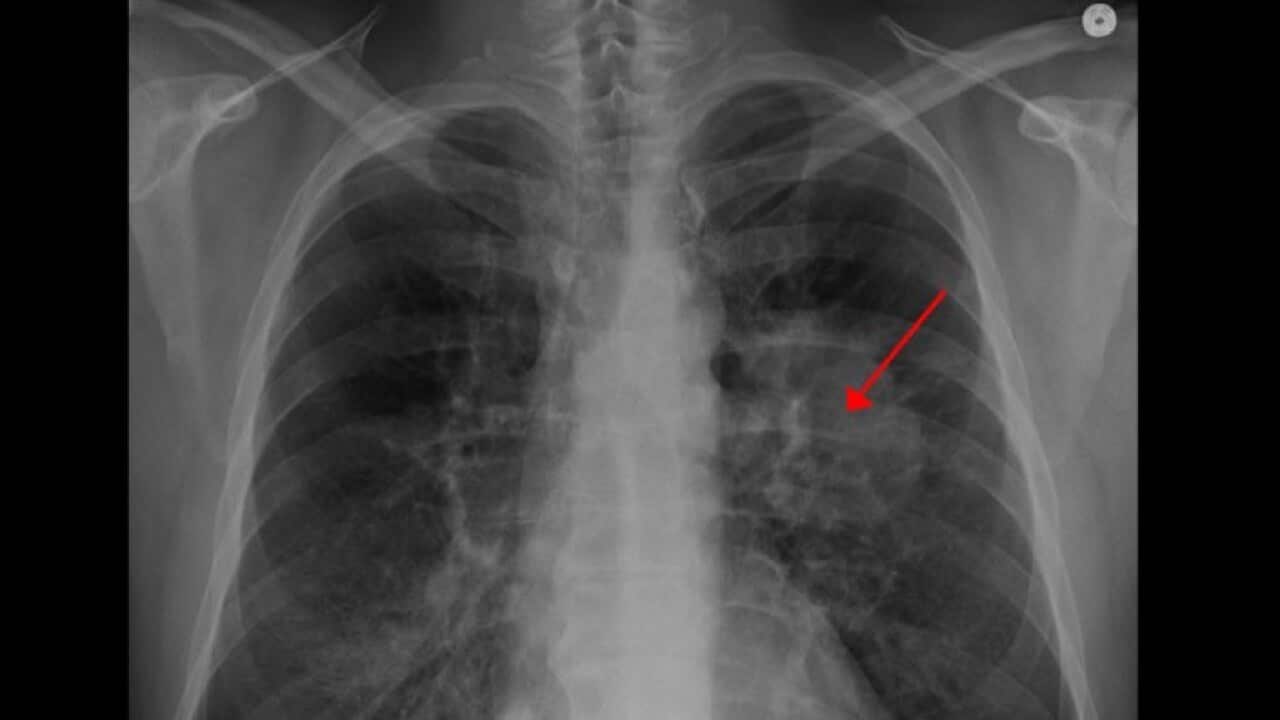

Рак плућа

Lung Cancer Credit: Wikipedia